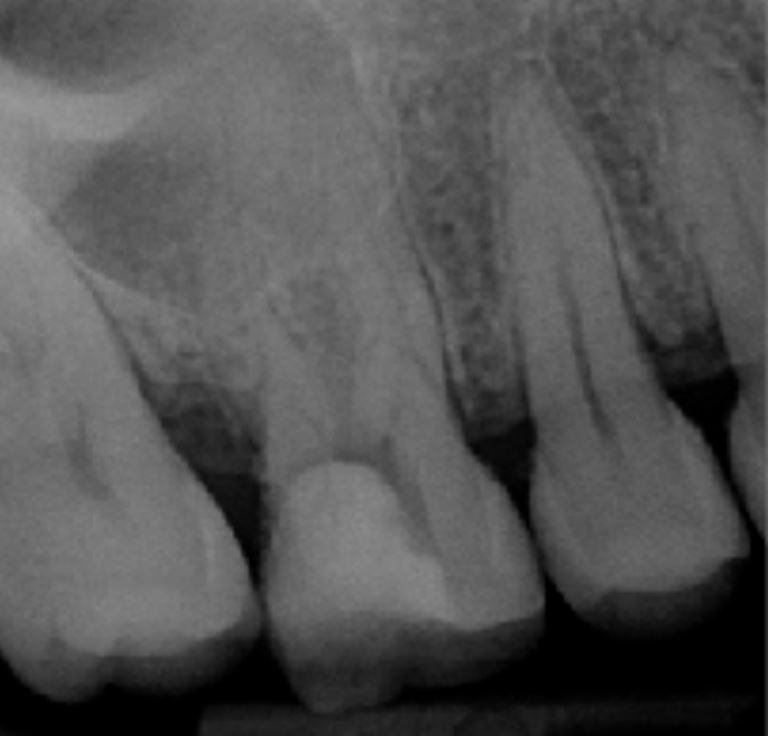

Caso clinico n. 2

Dr. Hetzel Rémy - Bourgoin Jallieu

"Trattamento iniziale del dente 16"

Radiografia preoperatoria

- Primo molare 16 che presenta un'immagine radiotrasparente in corrispondenza delle radici mesiali e palatine

- Test di vitalità negativo

- Medicazione in sede, dente aperto in pronto soccorso in ambiente ospedaliero